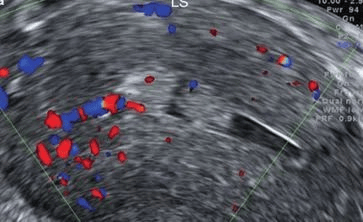

单发息肉典型超声表现为子宫肌层和内膜结构正常,宫腔内增强回声团,边缘连续光滑,外形规则,呈水滴状,在内膜较厚时,可见内膜形态不对称,息肉与正常内膜间界限清晰可辨,可见穿入性血流信号。

单发息肉典型超声表现为子宫肌层和内膜结构正常,宫腔内增强回声团,边缘连续光滑,外形规则,呈水滴状,在内膜较厚时,可见内膜形态不对称,息肉与正常内膜间界限清晰可辨,可见穿入性血流信号。